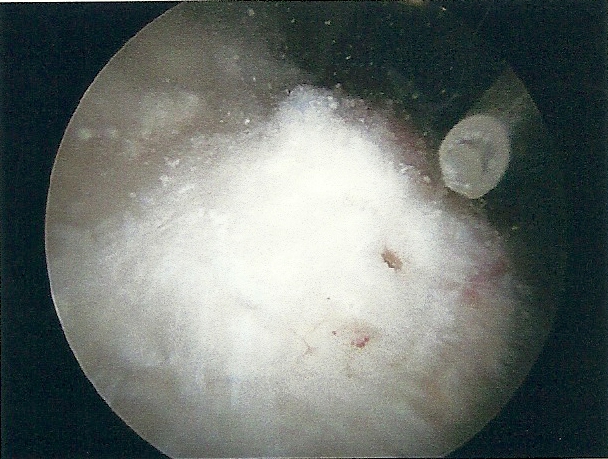

| All the Calcification |

|